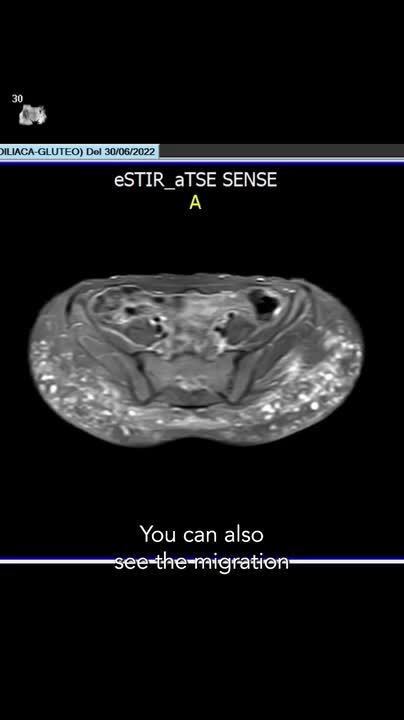

I understand that you don't want large scars, but health cannot take precedence over that, especially when opting for biopolymer removal surgeries with cannulas, which, as I have already informed you, offer no benefit to the patient.